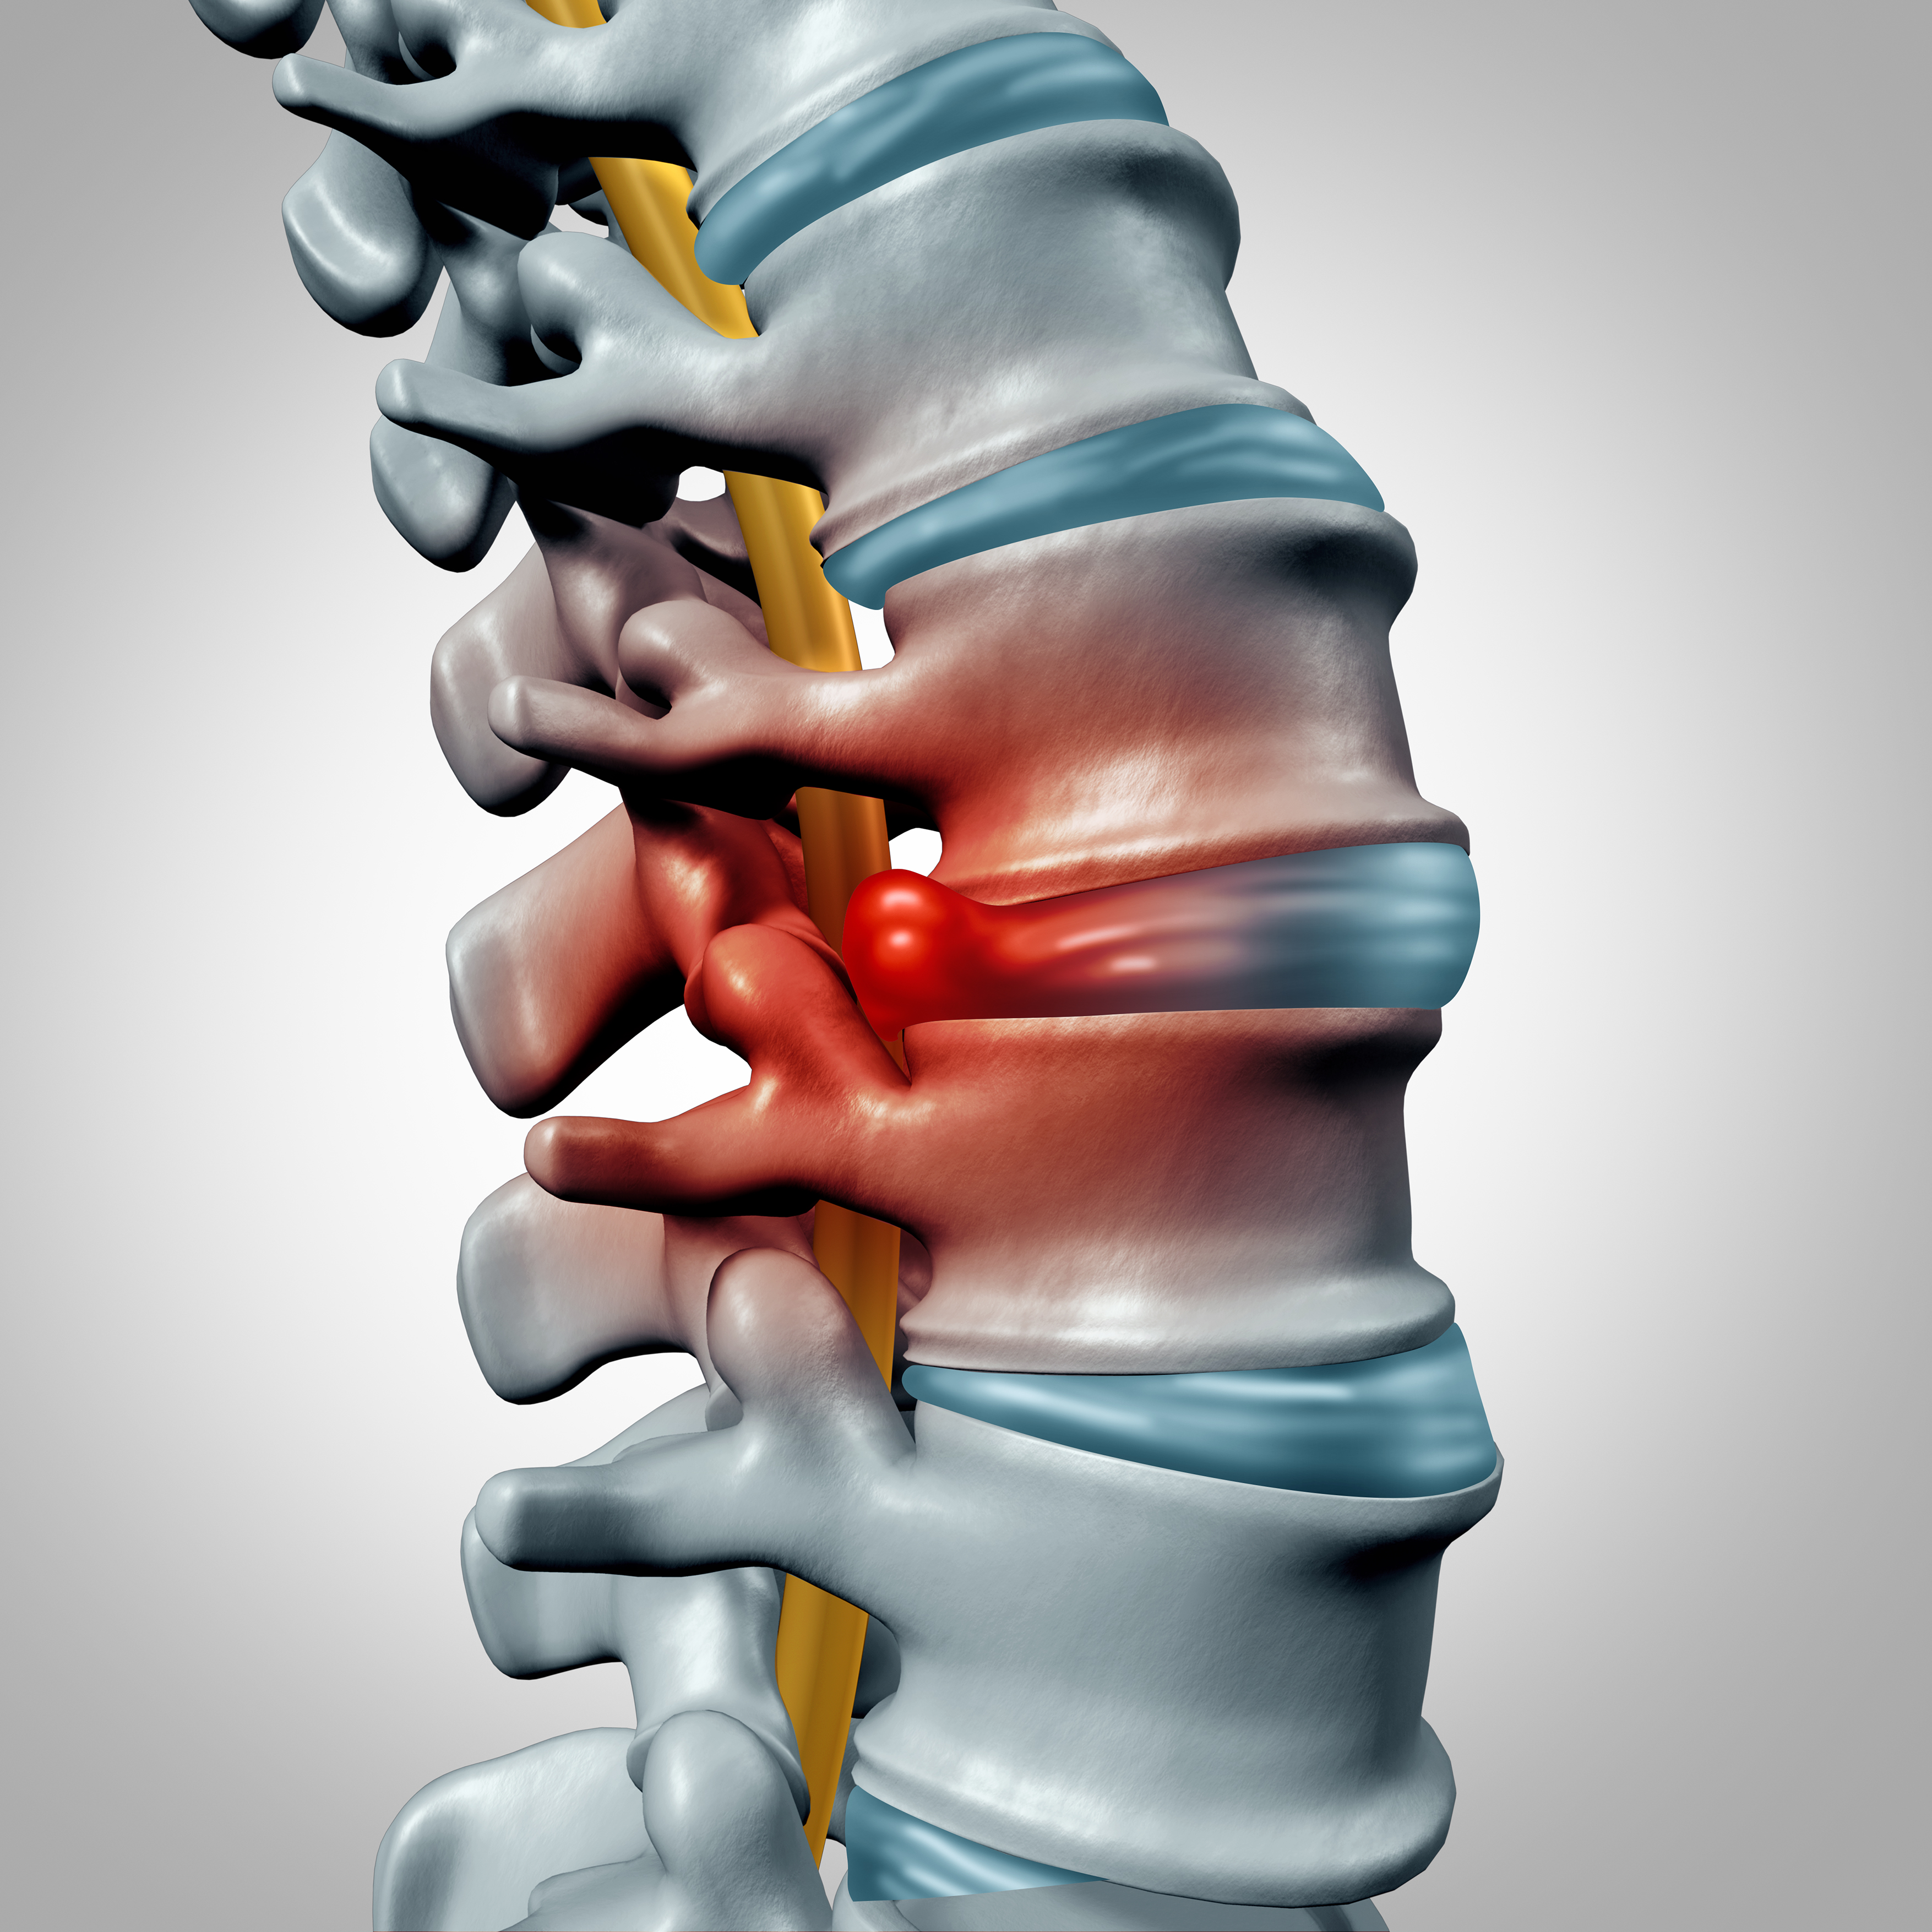

소위 디스크라고 잘 알려진 추간판탈출증은 척추뼈와 척추뼈 사이에 존재하는 추간판(디스크)이 어떤 원인에 의해 손상을 입으면서내부의 수핵이 밖으로 밀려 나와 주위 조직, 특히 척추신경을 압박하면서 통증 등의 증상을 유발하는 질환입니다.

요추 추간판 탈출증

· 다리가 찌릿찌릿하거나 당기는 듯한 통증

· 허리나 엉덩이 부위에 통증 발생

· 다리의 근력 저하 및 감각이상